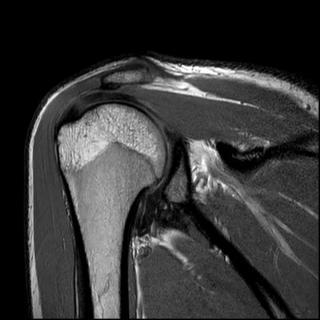

на фиг.5 - рентгенограмма коленного сустава в прямой и боковой проекции больного с начальными признаками остеоартроза; на фиг.6 - магнитно-резонансная томография коленного сустава больного, где отсутствует передняя крестообразная связка и наружная боковая связка; на фиг.7 - магнитно-резонансная томография коленного сустава больного, где показана восстановленная передняя крестообразная связка и наружная боковая связка; на фиг.8 - полное сгибание коленного сустава через три месяца после операции; на фиг.9 - стабильность коленного сустава через три месяца после операции.

На МРТ левого коленного сустава после операции в боковой и фронтальной проекциях: 10 - пластическое восстановление ПКС дупликатурой сухожилия длинной малоберцовой мышцы, 11 - пластическое восстановление малоберцовой коллатеральной связки сухожилием длинной малоберцовой мышцы, 12 - интерферентные шурупы (Фиг.7).